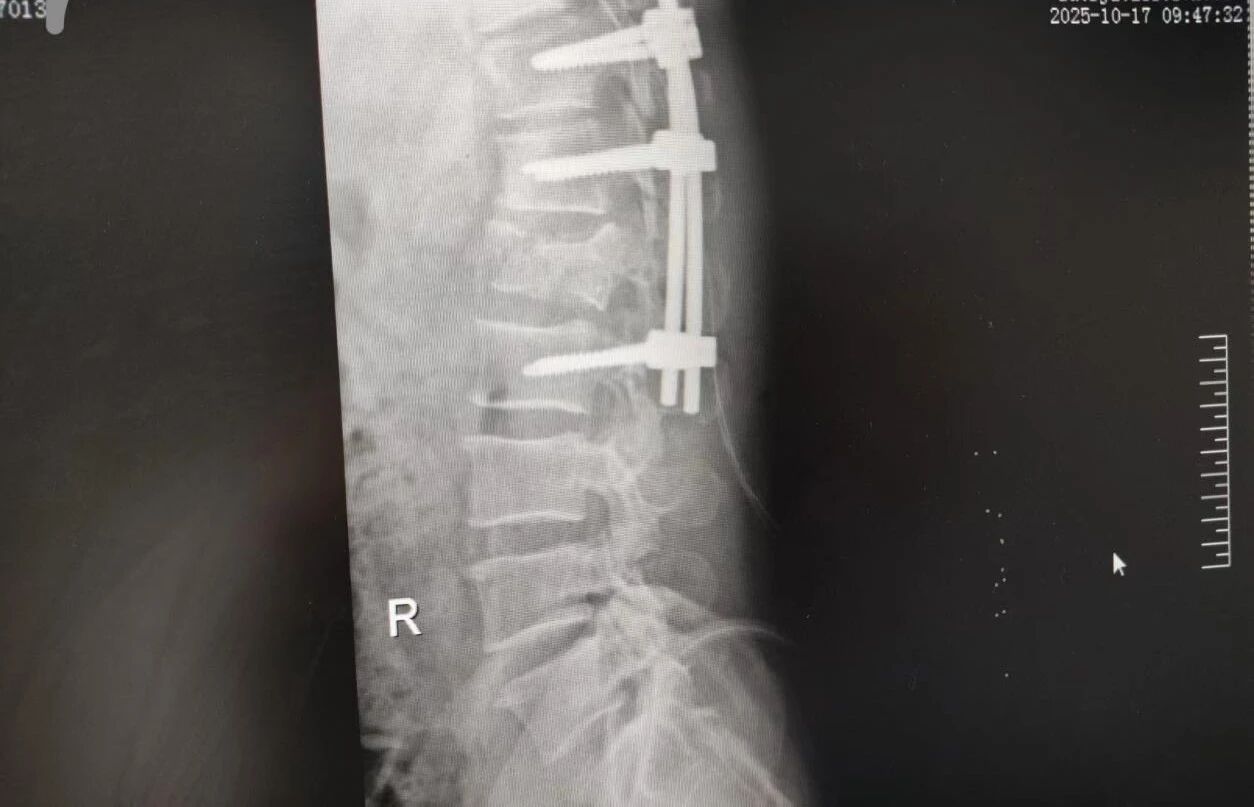

針對(duì)腰椎傷情,骨科竇志剛醫(yī)生團(tuán)隊(duì)緊急開展腰 1 椎體爆裂性骨折切開復(fù)位內(nèi)固定術(shù) + 椎板切除減壓術(shù)。手術(shù)室、麻醉科無縫銜接開通綠色通道,手術(shù)團(tuán)隊(duì)快速就位,術(shù)后患者下肢活動(dòng)恢復(fù)自如。